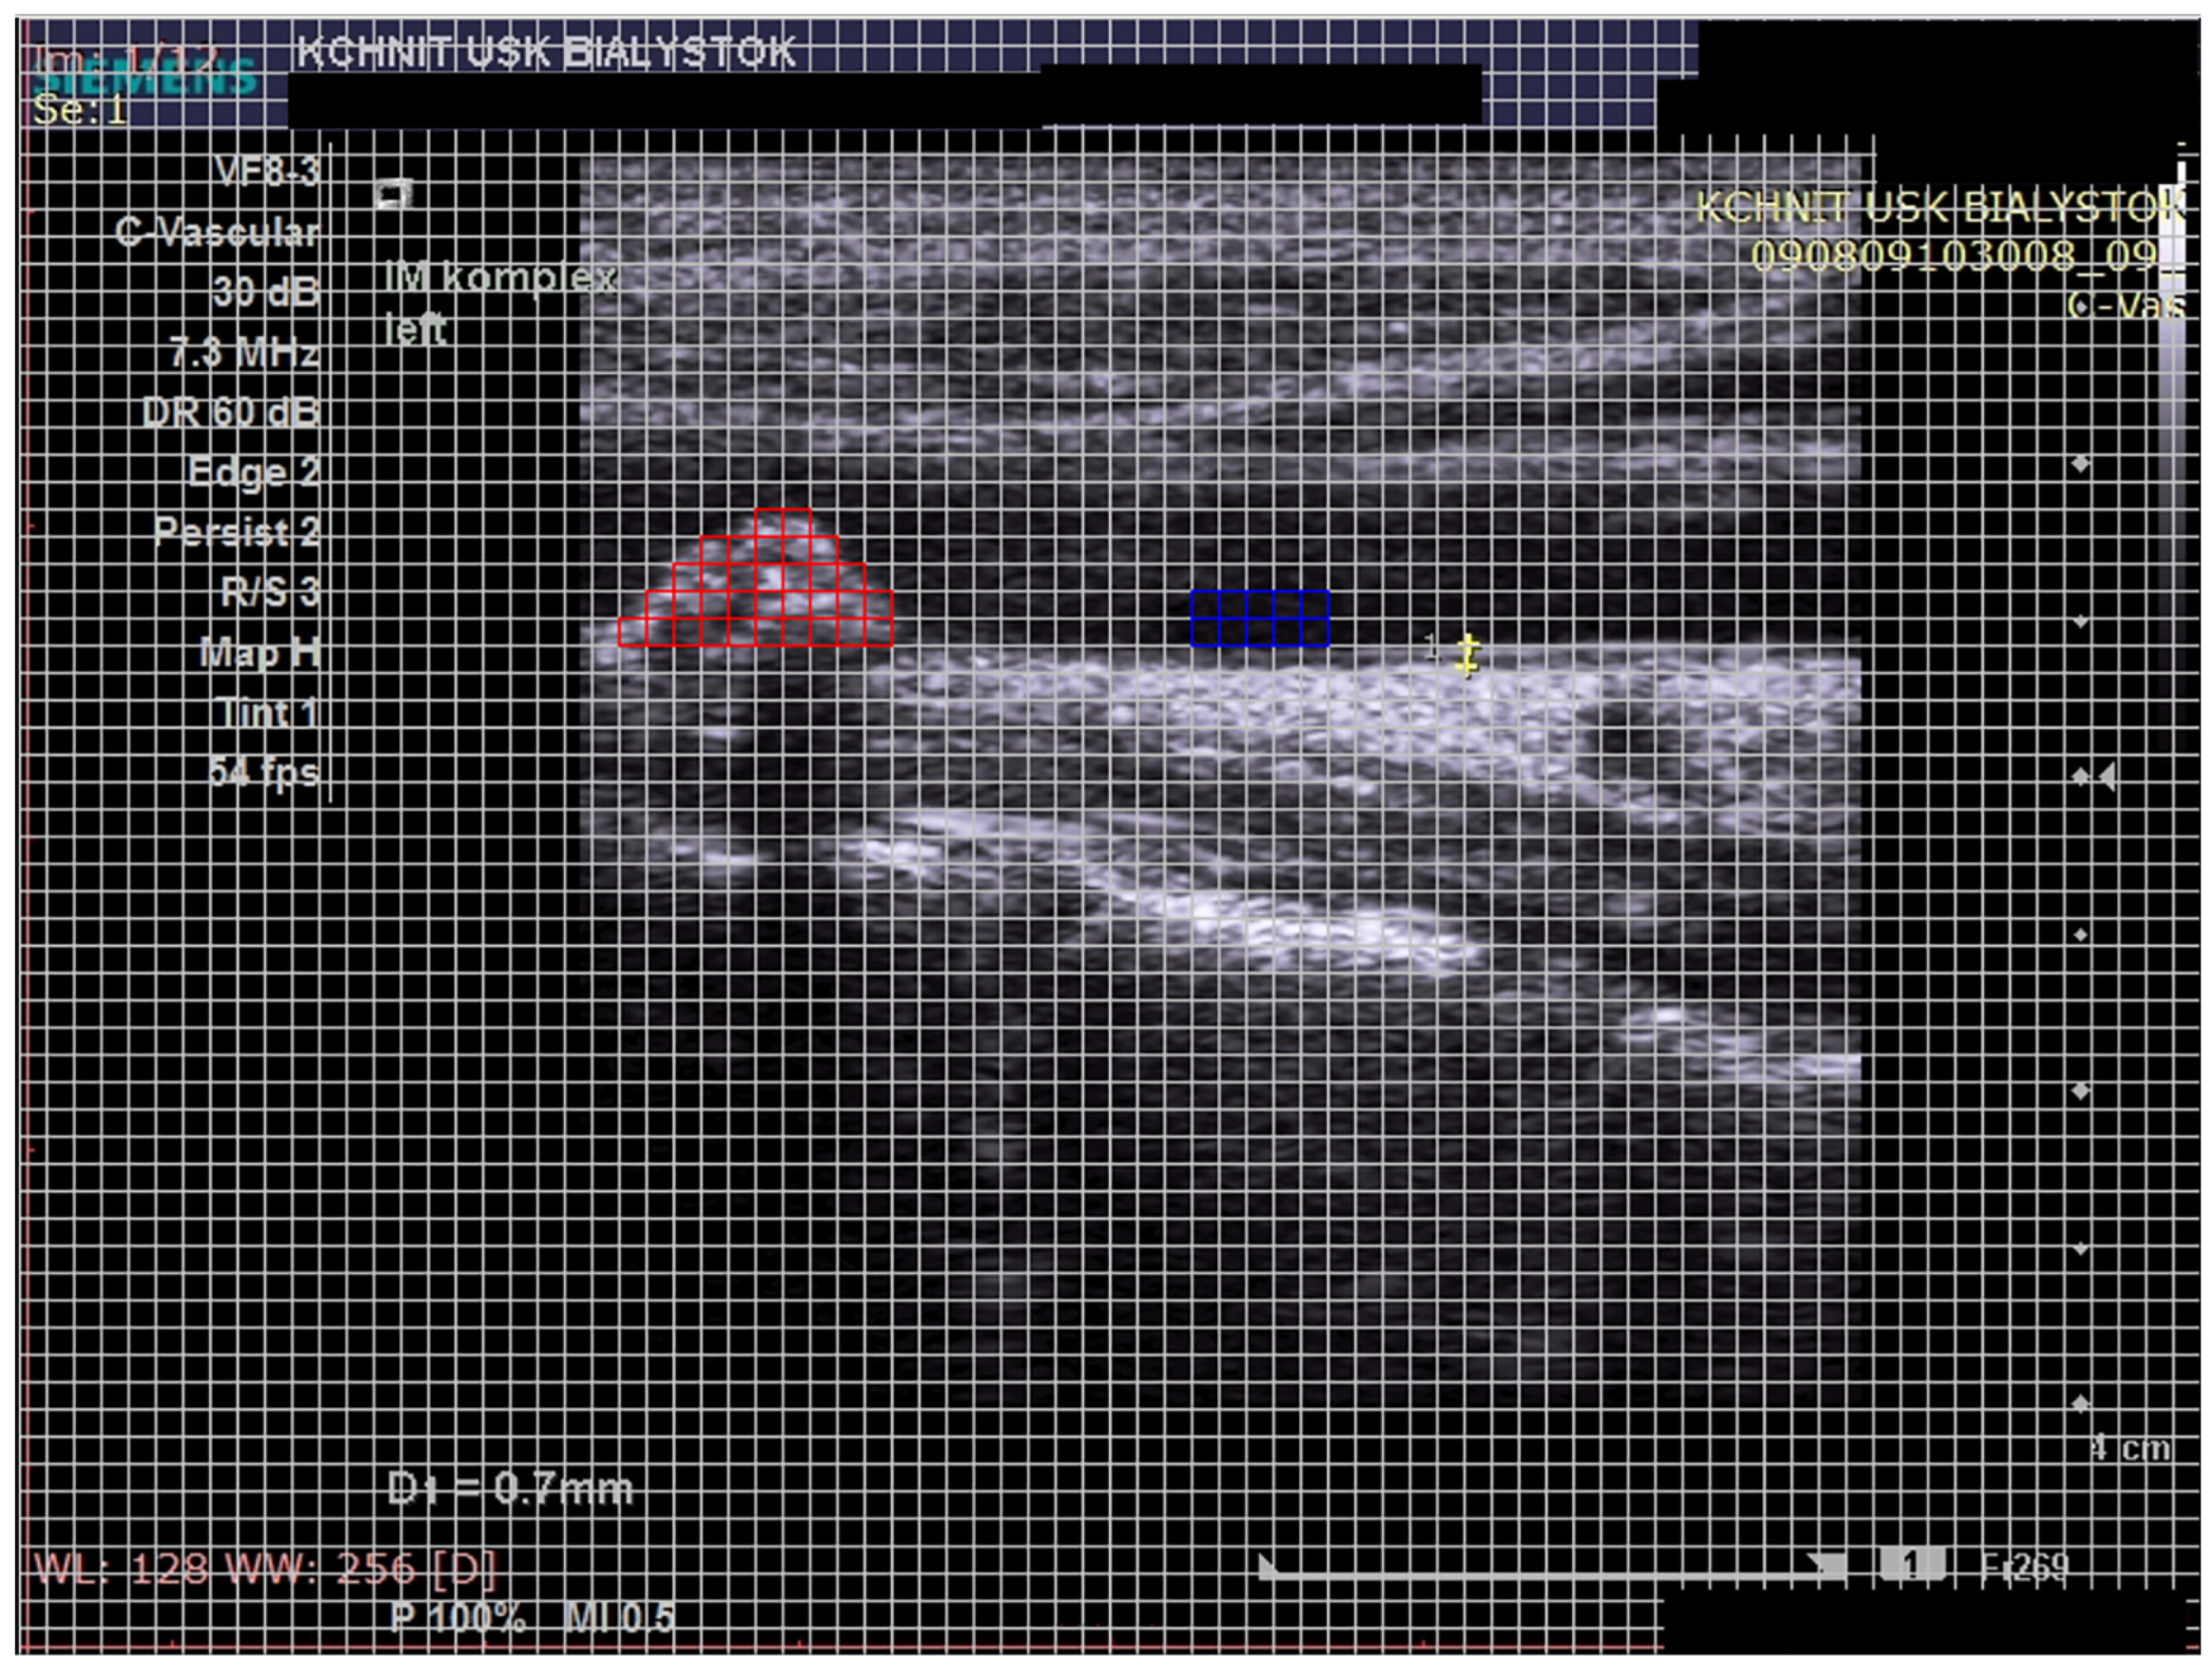

- Atherosclerotic plaque—during the ultrasound examination, the best possible image projection in B-mode presentation was selected with the entire atherosclerotic plaque visible—the image was not enlarged or brightened—according to the accepted standardization. The image of the plaque was recorded on a photograph. Then, to assess the atherosclerotic plaque, images from the ultrasound examination were used to analyze its structure on the GSM scale.

- Images of the visible atherosclerotic plaque in the carotid artery.